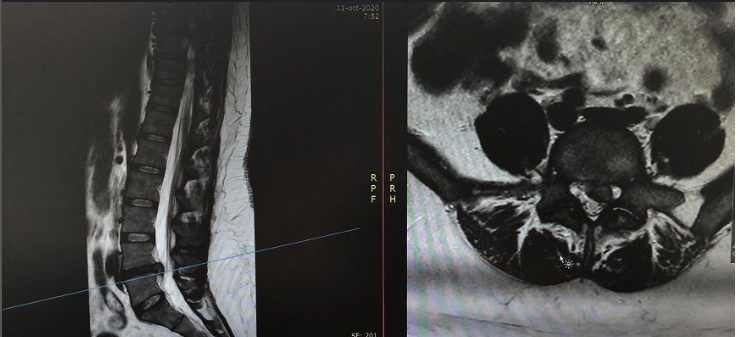

Paciente con IMC> 35% que ingresó por: ciática izquierda que no mejoró con tratamiento médico, presentó afectación vesical. Se decidió realizar la discectomía mediante la técnica MIS: tras la cirugía, la paciente mejoró su proceso doloroso y al día siguiente se retiró la sonda vesical. Es dada de alta a los dos días de ingreso en el Hospital.